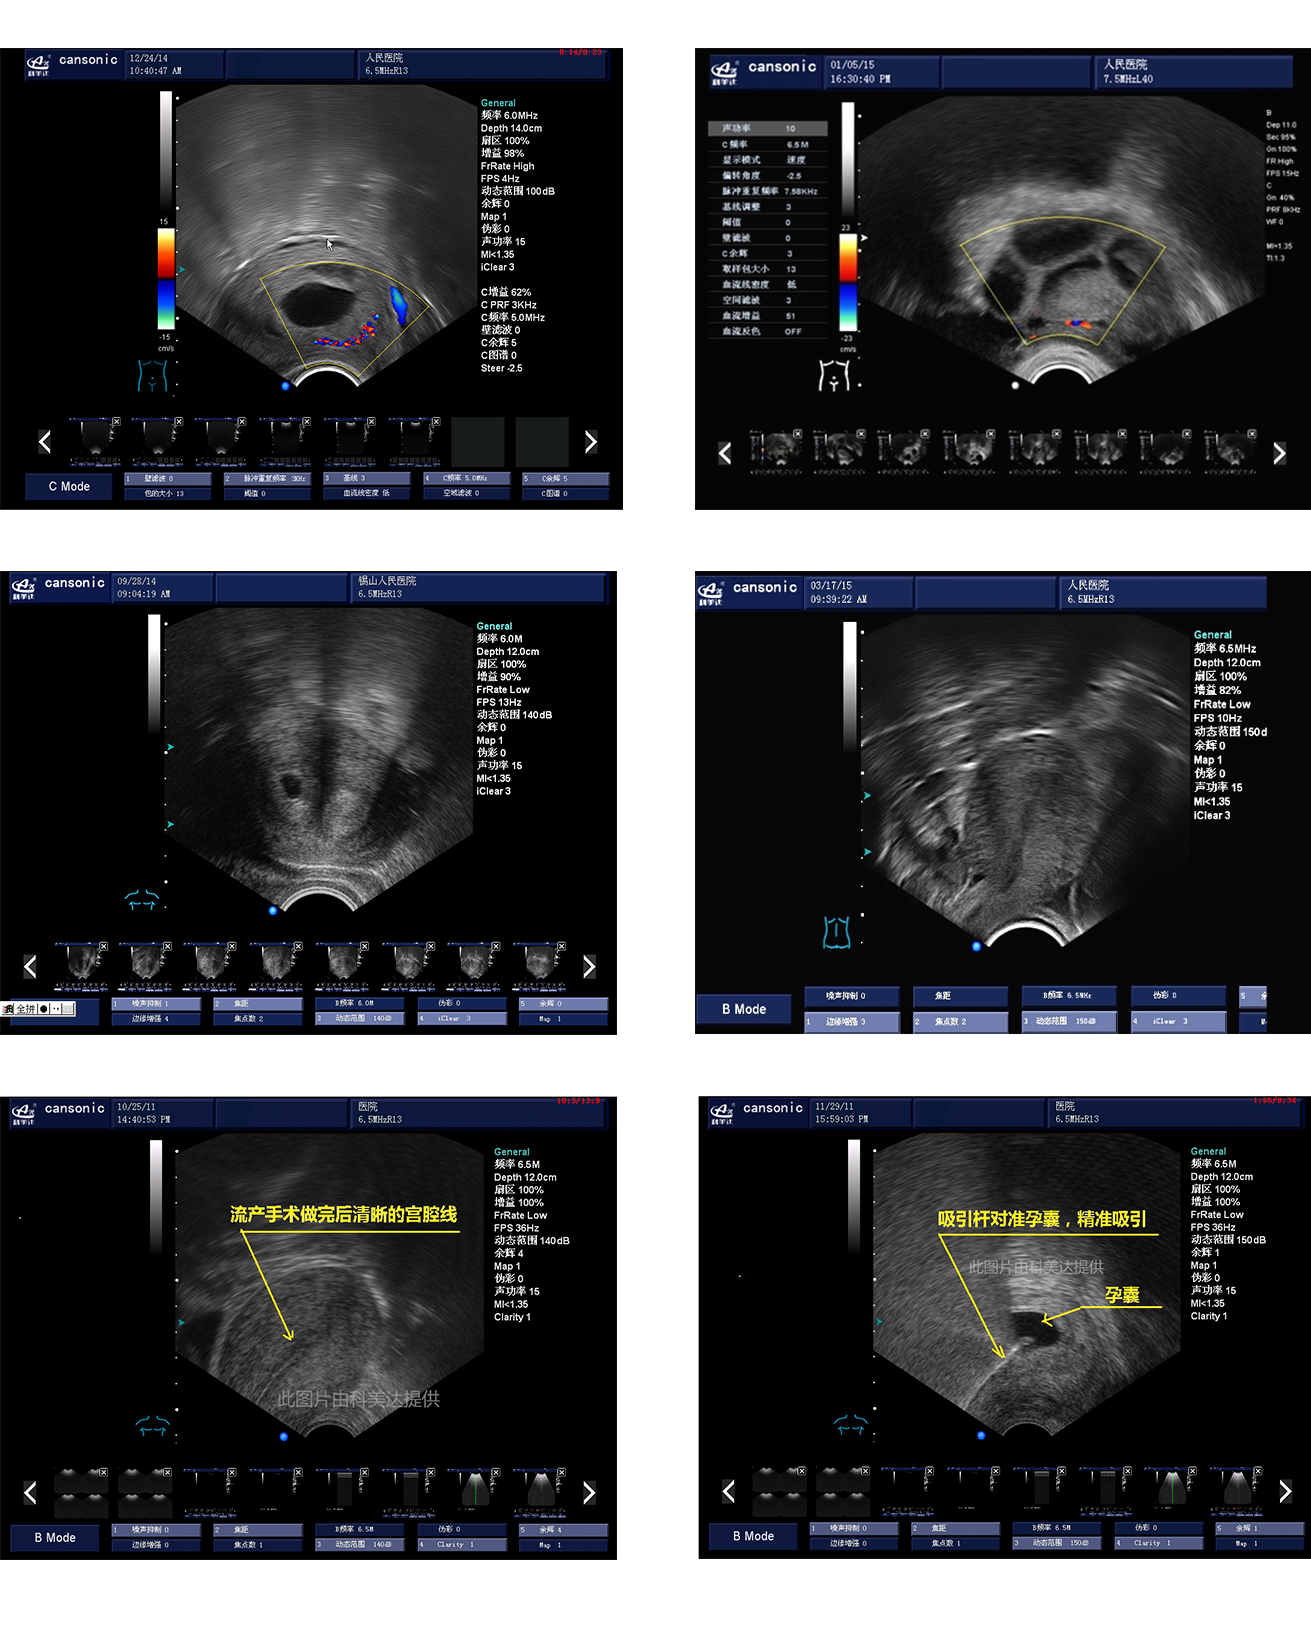

臨床圖示

1、采用高端彩超專業(yè)技術(shù),提供完整的宮腔手術(shù)監(jiān)測(cè)解決方案

3、血流靈敏度高,清晰可見